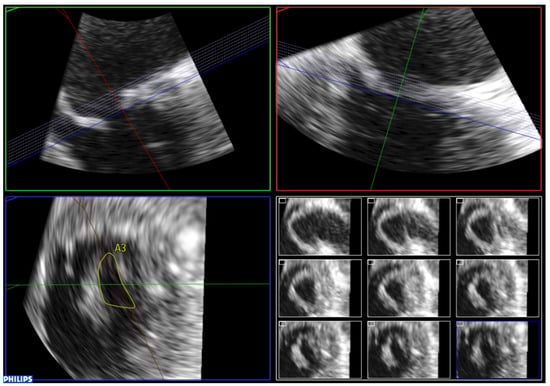

7.1. Simultaneous Biplane Imaging

7.2. Full Volume Imaging

7.3. Real-Time 3D Imaging

7.4. Focused Wide-Sector (3D Zoom) Imaging

| Anterior Leaflet | Posterior Leaflet | |||||

| Thickness (0–6) (0 = normal, 1 = thickened) | A1 | A2 | A3 | P1 | P2 | P3 |

| Mobility (0–6) (0 = normal, 1 = limited) | 0–1 | 0–1 | 0–1 | 0–1 | 0–1 | 0–1 |

| Calcification (0–10) (0 = no, 1–2 = calcified) | 0–2 | 0–1 | 0–2 | 0–2 | 0–1 | 0–2 |

| Subvalvular Apparatus | ||||||

| Proximal Third | Middle Third | Distal Third | ||||

| Thickness (0–3) (0 = normal, 1 = thickened) | 0–1 | 0–1 | 0–1 | |||

| Separation (0–6) (0 = normal, 1 = partial, 2 = no) | 0–2 | 0–2 | 0–2 | |||